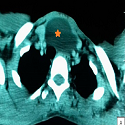

La sténose trachéale sévère post-intubation prolongée

Samia Frioui, Faycel Khachnaoui

PAMJ. 2017; 28: 247. Published 21 November 2017